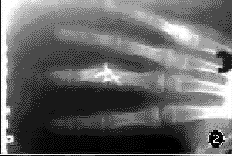

患者男,12岁。不慎被面条机绞砸伤左手,致左中指受伤,局部疼痛、肿胀、不能屈伸。伤后2h来我院就诊。检查:一般情况可,心肺检查无异常。左手肿胀,背侧皮肤挫伤约4.0cm×5.0cm。左中指指间关节肿胀,局部有压痛,可触及骨擦感,有异常活动,伸屈受限,末梢血运良好,手指无麻木感。X线检查:左中指指间关节畸形,中节指骨骨骺分离,近节指骨冠状面横形骨折,其骨折块位于关节腔外,伴有旋转移位(图1)。

图1左中指中节指骨骨骺分离,近节指骨冠状面骨折,旋转分离伴脱位